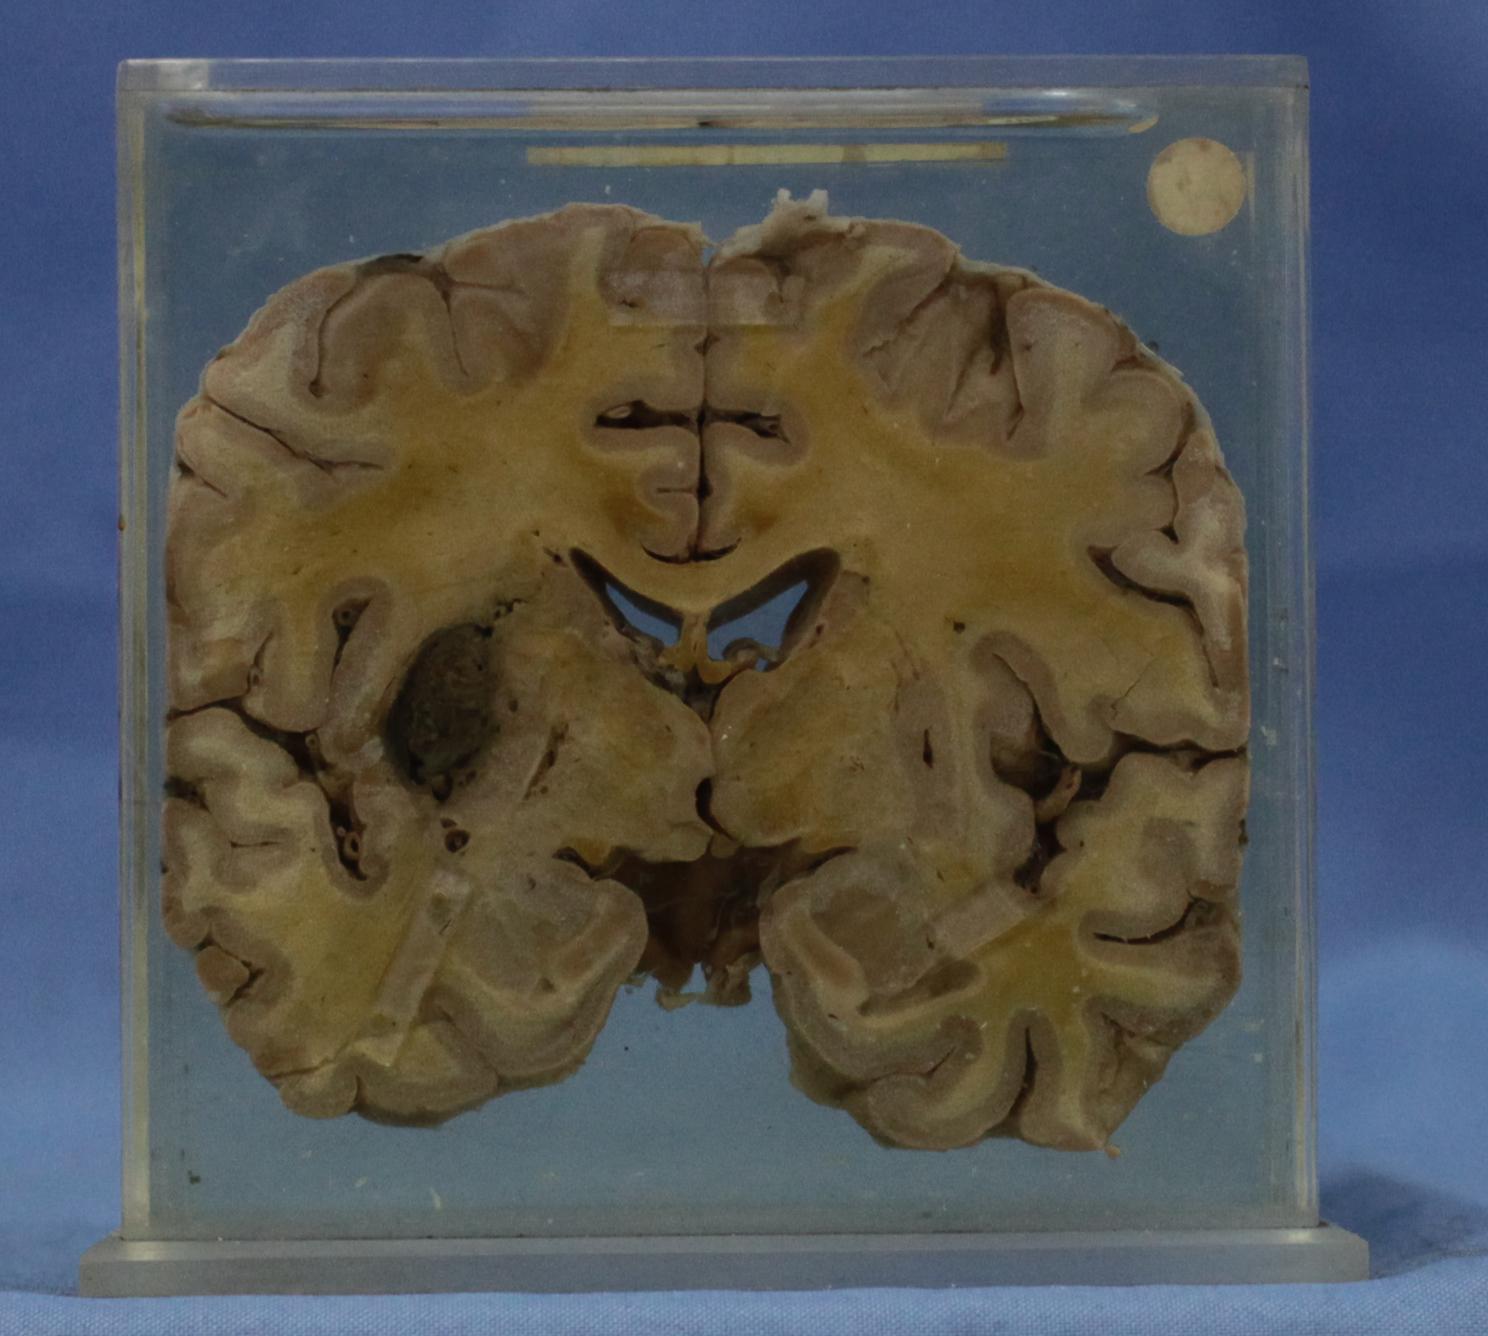

神经疾病-58-11. 基底动脉粥样硬化,左侧基底节外侧陈旧性梗死灶

经丘脑水平的脑水平切块,切块见丘脑外侧的基底核外侧凝血块直径2-3cm,并有含铁血黄素着色,局部组织破坏,同侧侧脑室变窄,基底面见硬化的动脉开口,切面口径变小,管壁见灰黄斑块。